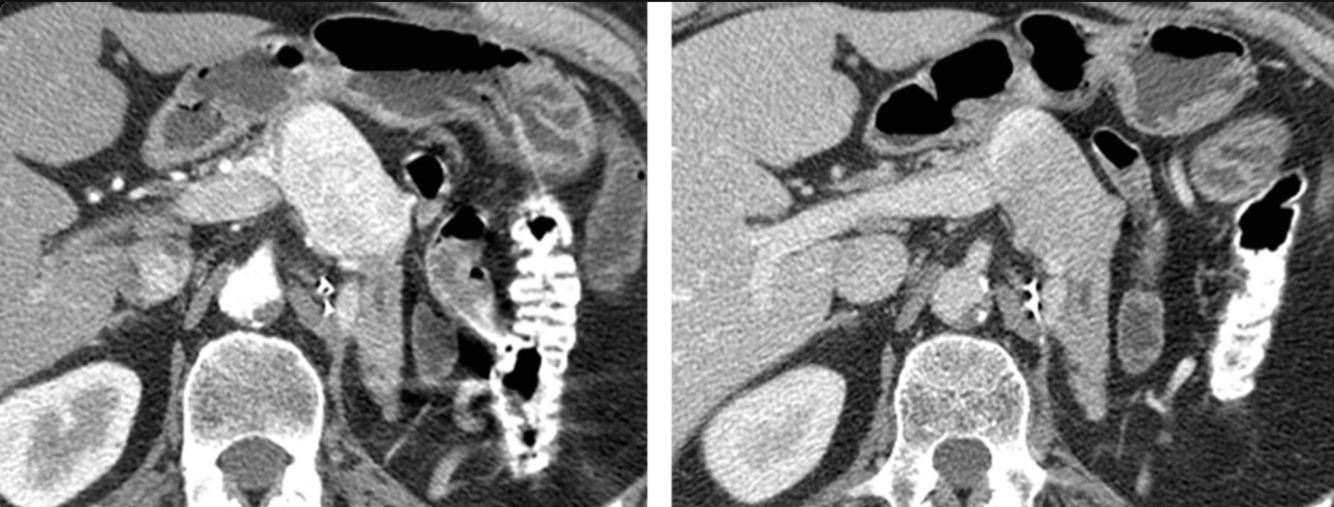

What is the most likely etiology for these findings?

Identify the following structures:

A: SMA

B: L renal vein

C: R renal artery